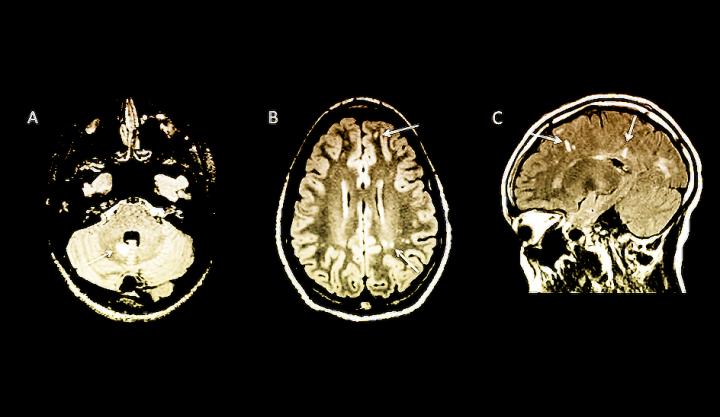

By the time multiple sclerosis (MS) is diagnosed in children, it may be difficult to prevent the disabilities and relapses that come with the disease. In a new Yale School of Medicine study, researchers examined MRI brain scans to identify children at high risk of developing MS before symptoms appear, which may lead to earlier diagnosis and treatment.

Published in the November issue of the journal Neurology: Neuroimmunology & Neuroinflammation , the study of 38 children at 16 sites in six countries showed that the MRIs can reveal changes in the brain associated with MS before the clinical symptoms of the disease appear in children.

The children in the study all underwent MRI scans for other reasons, most commonly headache, but the MRIs unexpectedly revealed signs of MS. Having MRI findings of MS without any symptoms of the disease has been termed radiologically isolated syndrome (RIS) and previously had only been seen in adults.

Approximately 42% of children in the study with MRI findings of MS developed the first clinical symptoms of the disease about two years after the abnormal MRI, which shows a faster development of the disease than has been reported in adults. Children who had a specific marker in spinal fluid or who had MRI changes in the spinal cord, were at greatest risk of developing the clinical symptoms of MS.